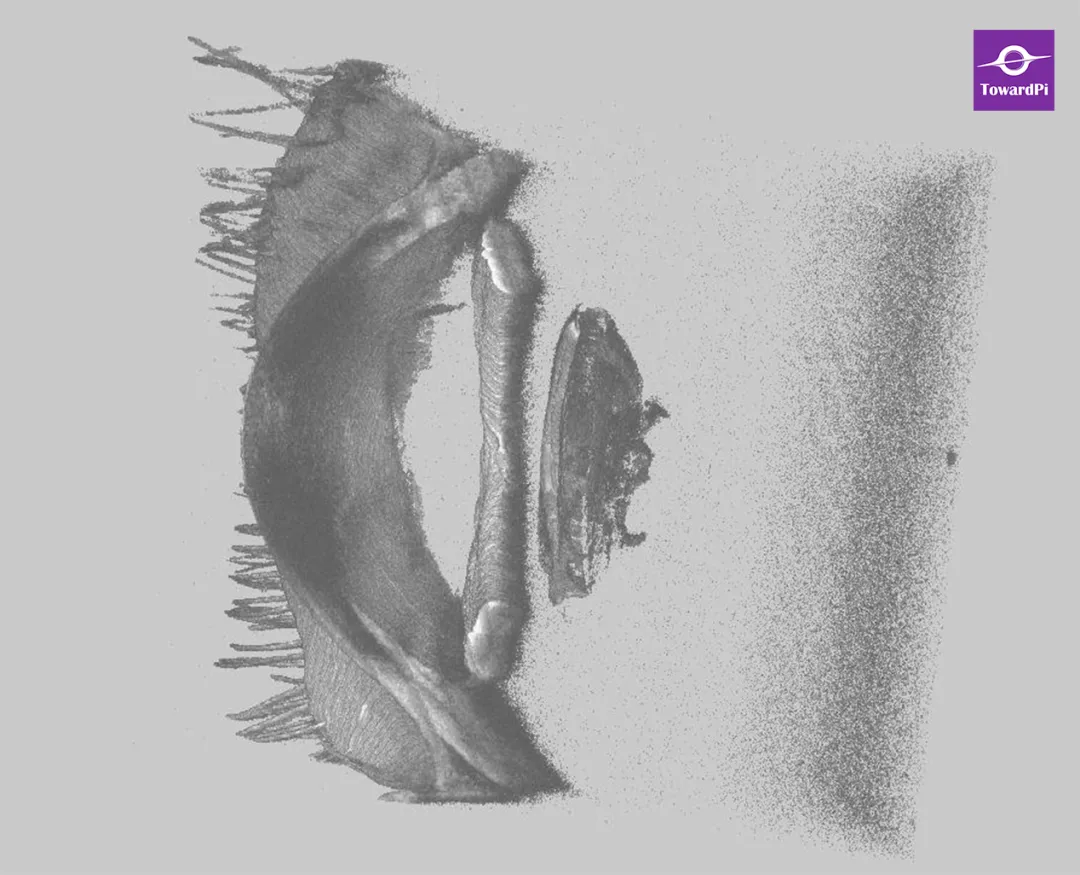

图1. IOL后表面与后囊膜之间存在间隙。

图2. 后囊可见锅巴样及空混浊泡。